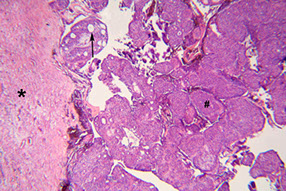

AOT c fibrous connective tissue capsule (*), nodular aggs of cells (#), and duct-like strucures (->)

Gland-like spaces surrounded by cuboidal to columnar cells (->)

AOT

Adenomatoid Odontogenic Tumor (AOT)

- aka adenoameloblastoma

Odontogenic tumor arising from enamel organ or dental lamina

- rare; seen in younger pts, 2F>1M; usually in anterior maxilla, and most are assoc c an impacted canine tooth

Imaging: radiolucency around an unerupted tooth extending past the cementoenamel junction

- usually has faint flecks of radiopacities surrounded by radiolucent zone

Gross: crown of tooth usually projects into cystic cavity

Micro: well-circ, central prolif of duct-like epithelium surrounded by small foci of calcification

- may see rosettes, trabecular or cribriform patterns of epithelium

- columnar-type cells c basal nuclei and clear cytoplasm can looklike pre-ameloblasts

- eosinophilic material seen in bwt tumor cells and in ductlike structures

Tx: enucleation